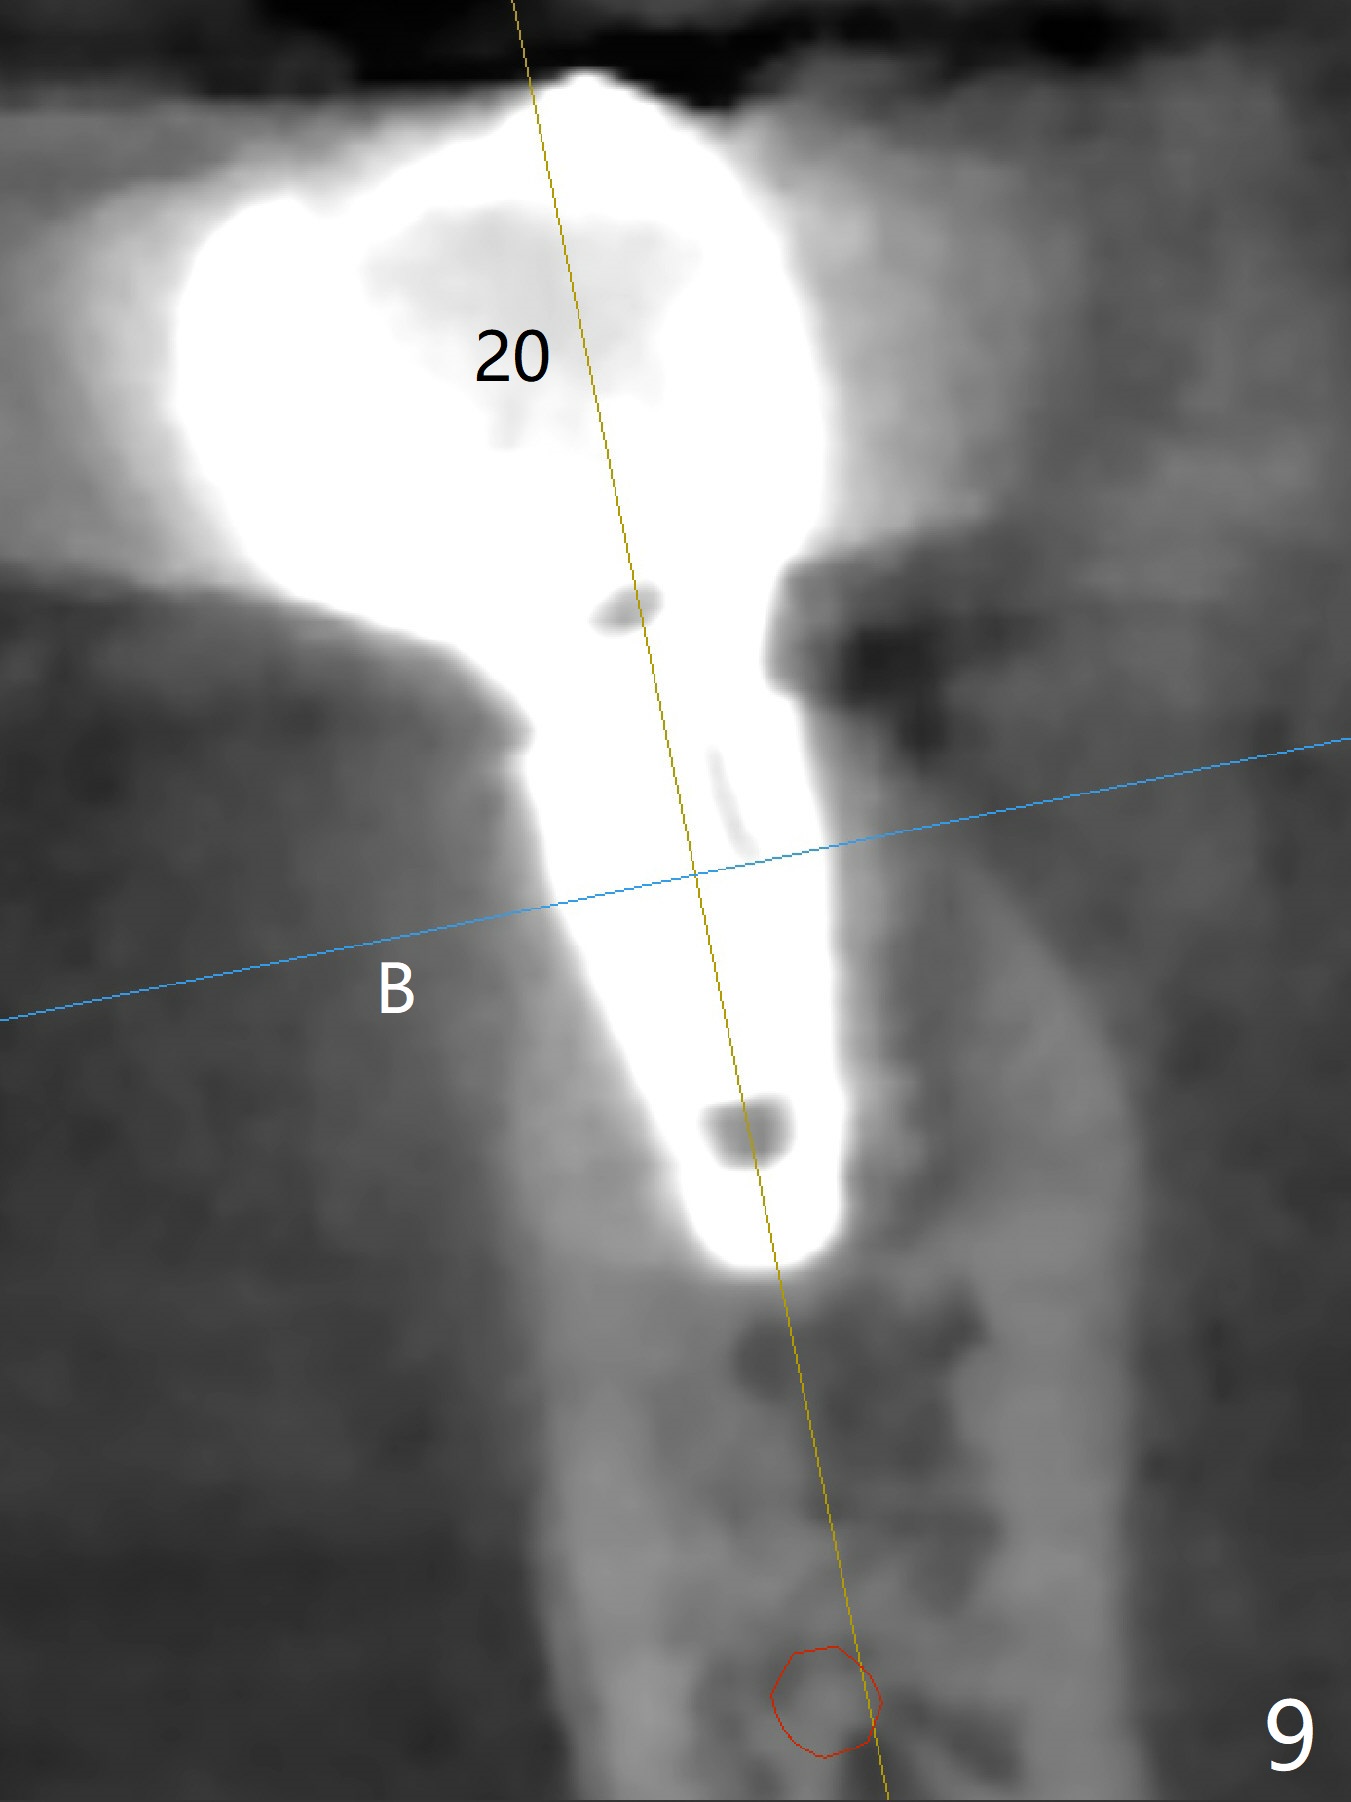

Five months post cementation, the patient returns because of loose abutment screw at #18. Bone resorption is noted (Fig.7 arrowheads). His oral hygiene is fair. He refuses implant at #2, saying that he dares not to chew on the left. When the screw became loose again 3 months later, he accepted the treatment. While he was returning to his home country, the lower right bridge was sectioned and the tooth #30 was removed. He is thinking of 2 implants at #29 and 30 (Fig.8). Bone loss appears not to get worse at #18-20 (Fig.9-11 (CBCT coronal sections, 2 years 7 months post cementation)). The implant at #19 is loose with a gap between the implant and the bone 3 years 5 months post cementation (Fig.12 *). SM implant does not last under stress (bruxism) and rigid implant/abutment connection.